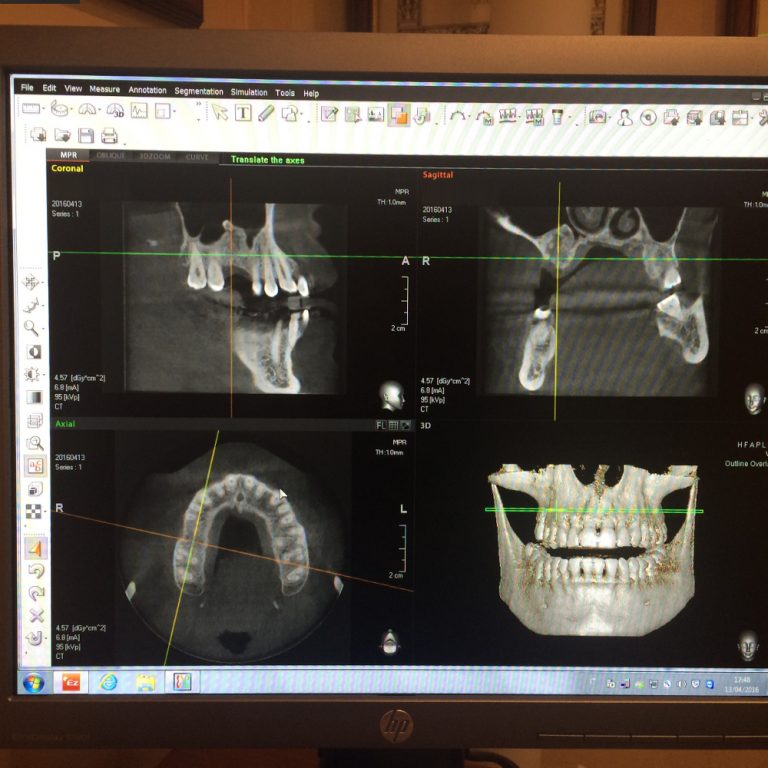

La Tac Cone Beam (Tomografia Computerizzata) è un’apparecchiatura in grado di scansionare le arcate dentali del paziente attraverso l’emissione di una dose molto bassa di raggi X e fornire immagini tridimensionali di altissima qualità delle ossa mascellari e dei denti.

La CBCT rappresenta il gold standard nel campo della radiodiagnostica odontoiatrica e sta alla base del grande successo dell’implantologia moderna.

La tomografia computerizzata è diventata l’esame più utile ai fini diagnostici e per la pianificazione di interventi di chirurgia implantare computer guidata e maxillo-facciale.

L’esame radiografico Dentalscan Cone Beam è un esame semplice e veloce. Il paziente si posiziona in piedi al centro della macchina e l’operatore provvede a orientare la testa del paziente in modo che il mento appoggi su un piano e contestualmente morda una placchetta per tenere fisse le due arcate dentarie. La parte superiore della macchina girerà attorno alla testa del soggetto allo scopo di raccogliere le informazioni riguardo alle arcate dentarie. Tali informazioni verranno utilizzate da un software che fornirà la rappresentazione tridimensionale delle ossa e dei denti. Con la tomografia computerizzata Cone Beam 3D, non solo si riescono ad avere immagini più nitide e precise rispetto alle vecchie TAC, ma è stato anche possibile ridurre fino al 90% la quantità di raggi generati e di conseguenza quelle assorbite dal paziente. La durata complessiva dell’esame può variare da 6 a 15 secondi ed è possibile stabilire se scansionare un solo dente, una sola arcata oppure entrambe le arcate contemporaneamente. Le moderne tecniche odontoiatriche come l’implantologia computer guidata, con protesi a carico immediato non potrebbero essere effettuate senza l’ausilio della tomografia computerizzata CBCT in fase diagnostica e di progettazione per il posizionamento degli impianti dentali.